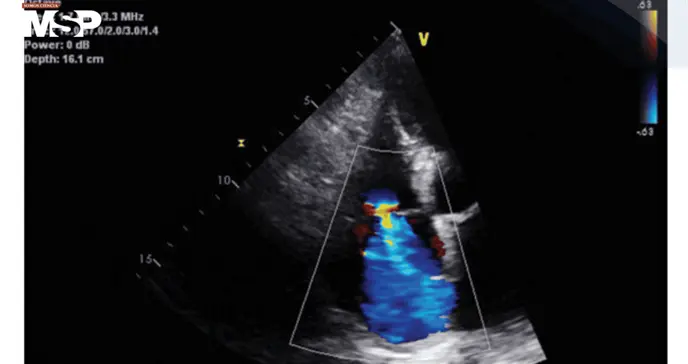

Los estudios iniciales descartaron patología intracraneal aguda, pero el ecocardiograma reveló hipertensión pulmonar, regurgitación tricuspídea severa, dilatación de la aurícula derecha y fracción de eyección preservada. En la piel se observaban petequias bilaterales en extremidades inferiores, junto a los signos marcados de malnutrición.

Ante la combinación de síntomas cardiopulmonares sin etiología clara, un cuadro neuropsiquiátrico agudo y signos dermatológicos compatibles, se consideró la posibilidad de escorbuto.

Los niveles séricos de vitamina C confirmaron la sospecha al encontrarse indetectables. La paciente inició suplementación intravenosa de ácido ascórbico, experimentando una mejoría progresiva de la disnea y del estado mental.

Tras ocho días de hospitalización fue dada de alta, aunque se perdió el seguimiento ambulatorio, lo que impidió demostrar ecocardiográficamente si la hipertensión pulmonar había revertido con la terapia.

En la primera paciente, la profunda deficiencia de vitamina C ofrecía una explicación plausible para la hipertensión pulmonar en ausencia de otras causas estructurales o autoinmunes.